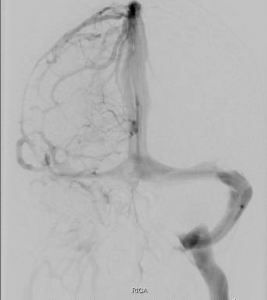

Case Study 1

55 year-old female deaf since childhood. 2 year history of ear pain, dysarthria, and dysphagia. Examination reveals tongue deviation to the right with hemiatrophy, decreased gag, right shoulder droop.

• Arteriogram 1

• Arteriogram 2

• Arteriogram 3